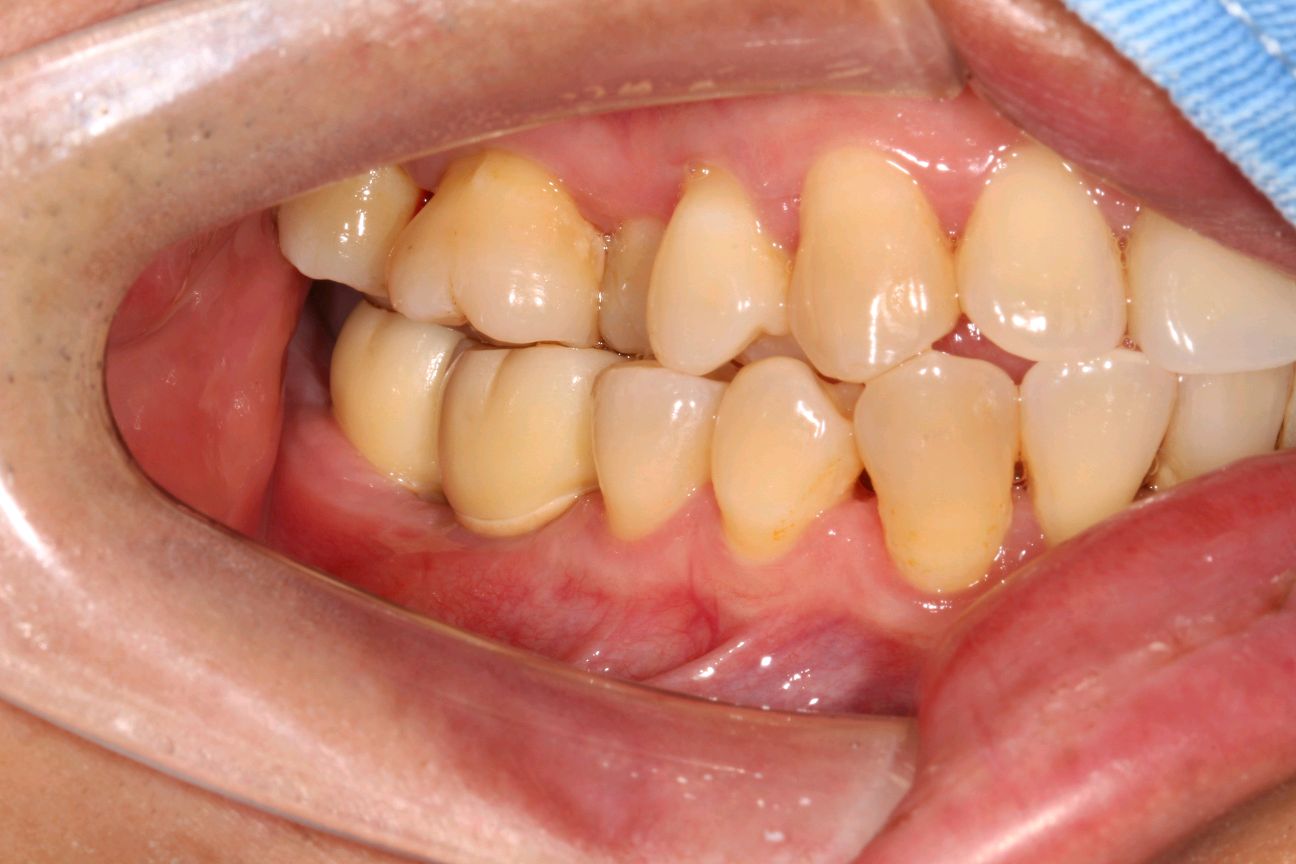

术后